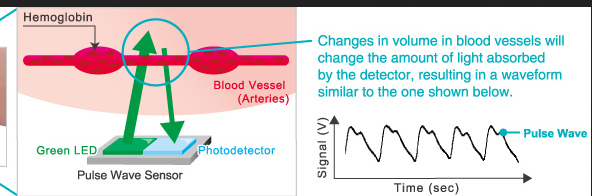

36 blood software